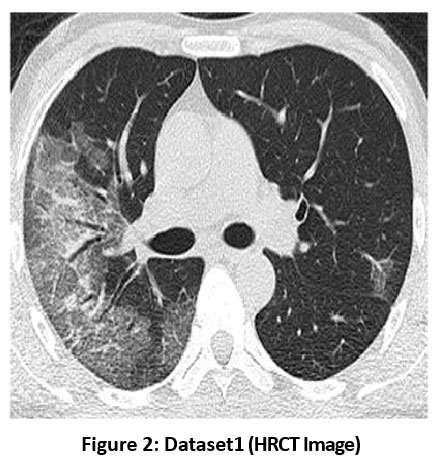

![]() |

Figure 2: Dataset1 (HRCT Image) |

Figure 2 shows the dataset1, which is chest HRCT. In HRCT imaging, lung tissue is scanned in narrow slices of 1-2 mm, which enables minimal changes in the parenchyma and gives a relatively good portrayal of lung architecture. Its late phase is the most suitable for assessing lung conditions as it provides a higher resolution and contrast.